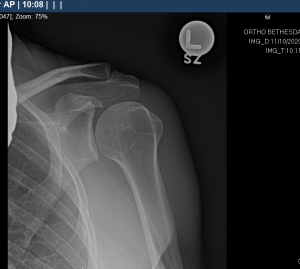

The initial evaluation involves a history, physical exam and usually specific x-ray views to assess the bone pattern and integrity of the shoulder. The treatment will often involve rest, heat, oral anti-inflammatory (non-steroidals such as Advil and Aleve), cortisone injections in specific areas of the shoulder and eventually physical therapy. These treatments work gradually and require patience by the physician and the patient. Somewhere between 50-80% of patients even with full thickness tears can respond at least partially to non-operative treatment. There is no evidence to support the use of platelet rich plasma, human growth hormone or stem cells as a non-operative treatment for rotator cuff tears or as an adjunct to surgery for rotator cuff tears. There are some patients who do not respond to appropriate non-operative treatments and they require further evaluation.

The most commonly used test to evaluate the integrity of the rotator cuff is the MRI (magnetic resonance imaging). There is an assumption by the public that MRI testing is very exact and dependable. This is not always the case. MRIs like all tests are dependent on the quality of the MRI machine and the computer software that is used as well as the interpretive skills. In general, larger magnet and non-open MRI give superior images. Specific magnetic coils for certain body parts improve the imaging. Even given this, it is estimated that over half of partial thickness tears are not found on conventional MRI. Reports presented at the American Academy of Orthopaedic Surgeons meetings indicate that MRI differentiates full from partial thickness tearing only part of the time. When needed, to improve accuracy, an MRI arthrogram (gadolinium is injected into the shoulder joint, not intravenous gadolinium) has significantly improved the accuracy of the test. The high false positive test rate with MRI without gadolinium injection may have led to many people having surgery for what is suspected to be a full thickness tear when they only had a partial thickness tear.